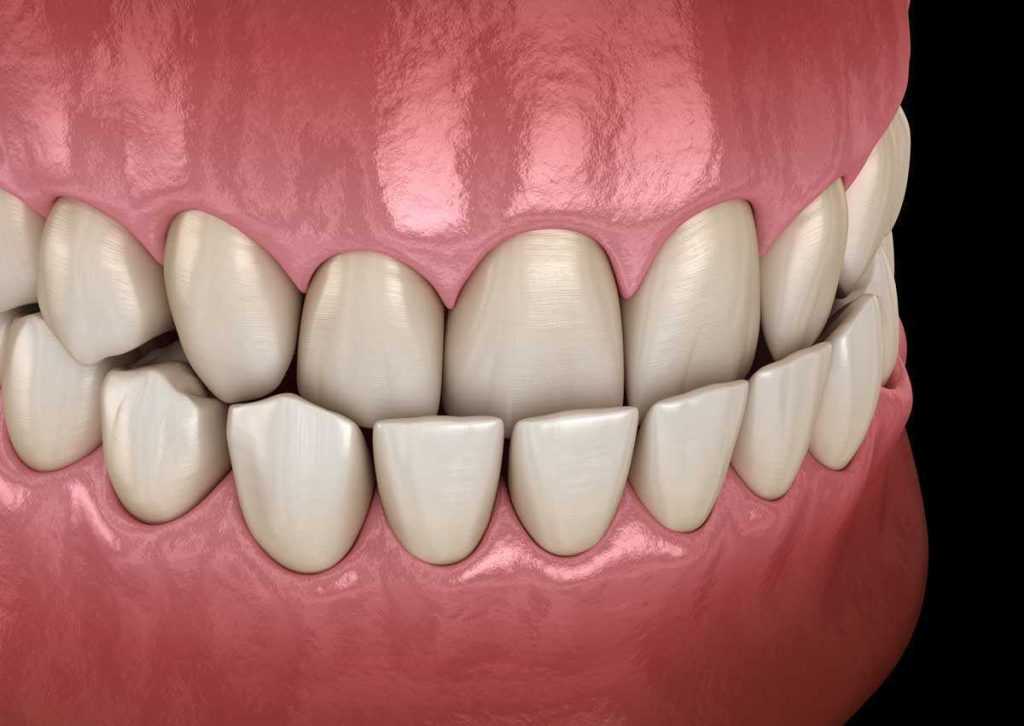

Zbijenost zubi

Zubi se međusobno “guraju”, preklapaju, kao da nemaju dovoljno mjesta. To je posebno često uočljivo na prednjim zubima gornje i donje čeljusti.

Duboki zagriz

Kod dubokog zagriza zubi gornje čeljusti uvelike prekrivaju donje zube. Ponekad se donji zubi gotovo i ne vide. Takvi zubi će se pojačano trošiti.

Izbačenost donje čeljusti (progenija)

Također vrlo česta nepravilnost zagriza koja ima mnogo varijanti. Ono što je karakteristično za ovu ortodontsku anomaliju jest da se gornji zubi nalaze iza donjih.

Otvoreni zagriz

Gornji i donji zubi ostaju međusobno udaljeni čak i kada osoba zatvori čeljust. Ova ortodontska anomalija može stvarati ozbiljne funkcijske probleme.